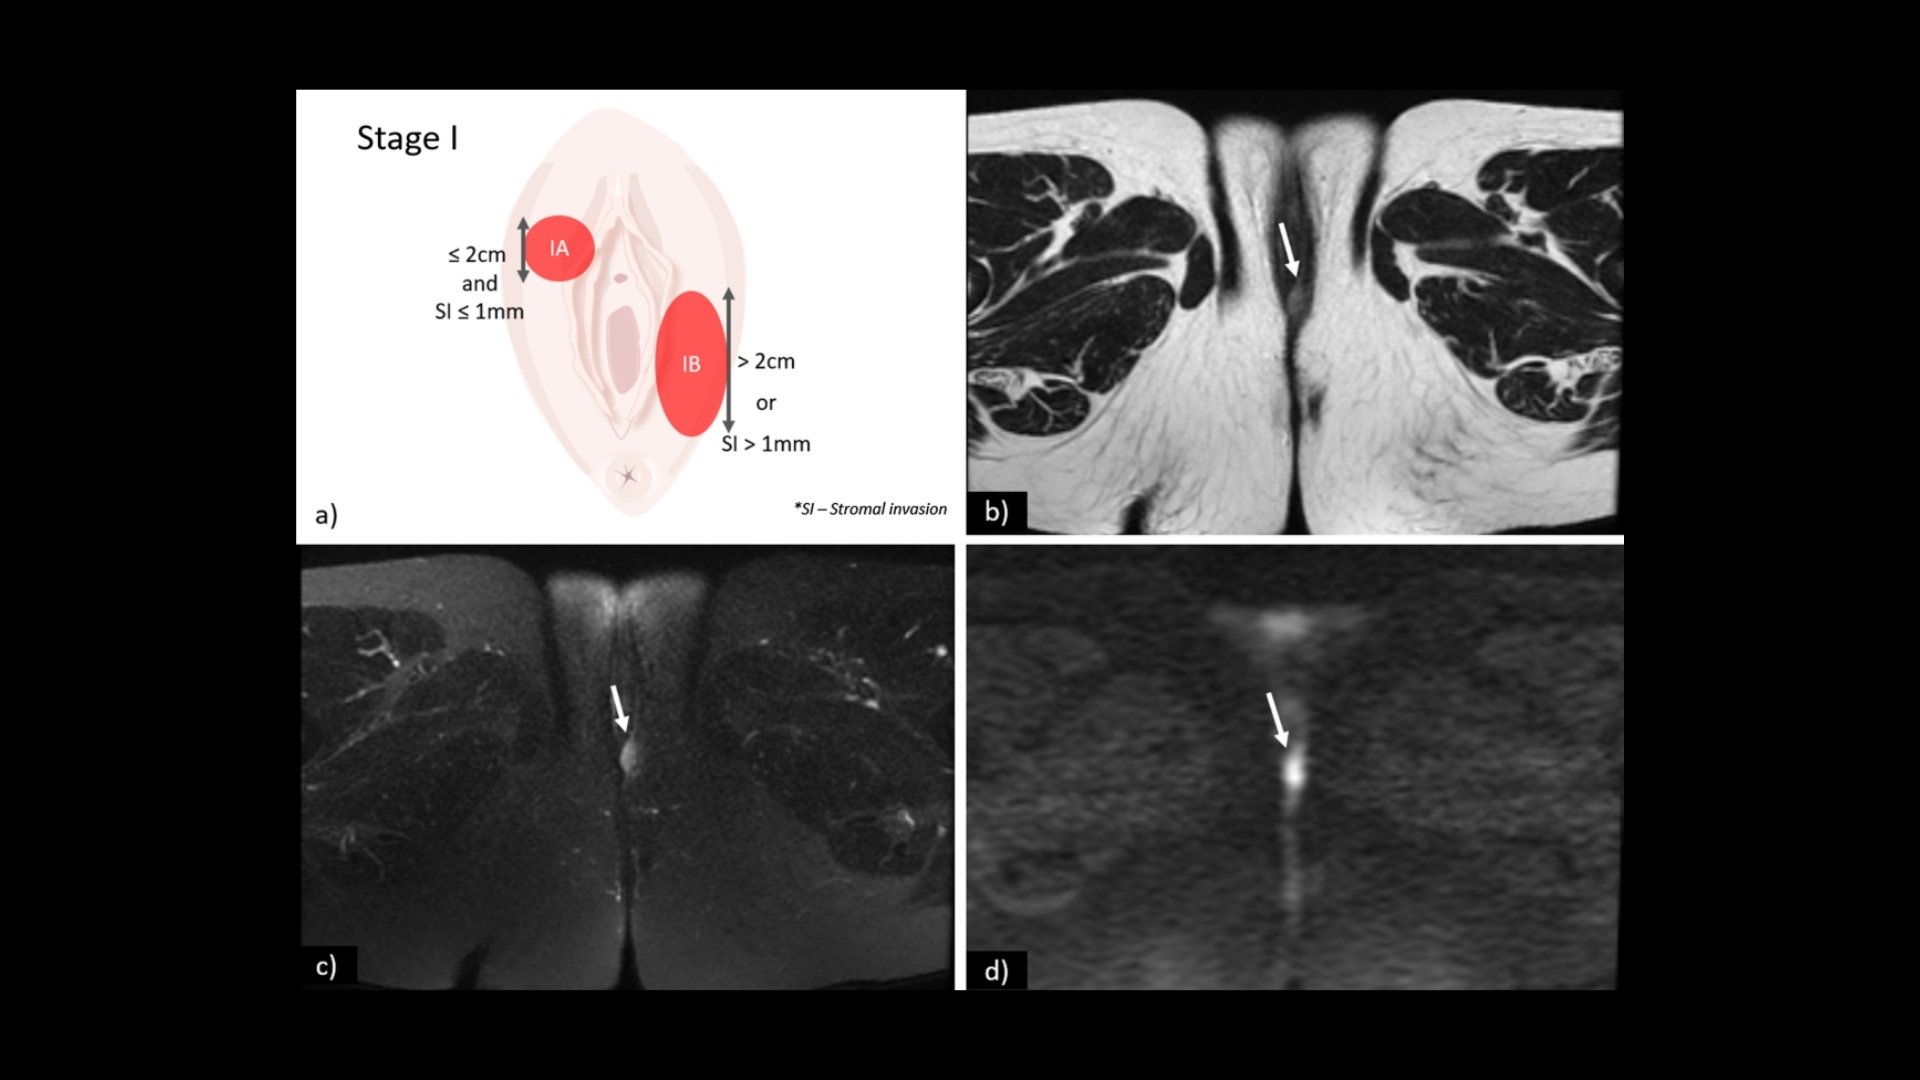

第 1 期 - 外陰癌 (Vulvar Carcinoma)

在第一階段,腫瘤完全位於外陰,直徑通常小於 2 公分。

• 腫瘤局限於外陰皮膚或下層組織。

• 未發現淋巴結受累或遠端擴散。

• 治療選擇:手術切除、放射線治療,以及結合代謝腫瘤學的綜合方法。

• 結果:五年內的存活率超過 90%,強調早期發現的意義。